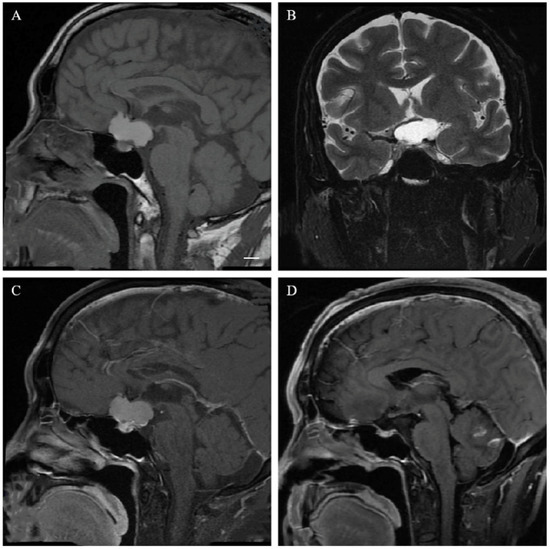

2.3. Neuroradiological Evaluation

3.2. Neuroradiological Features